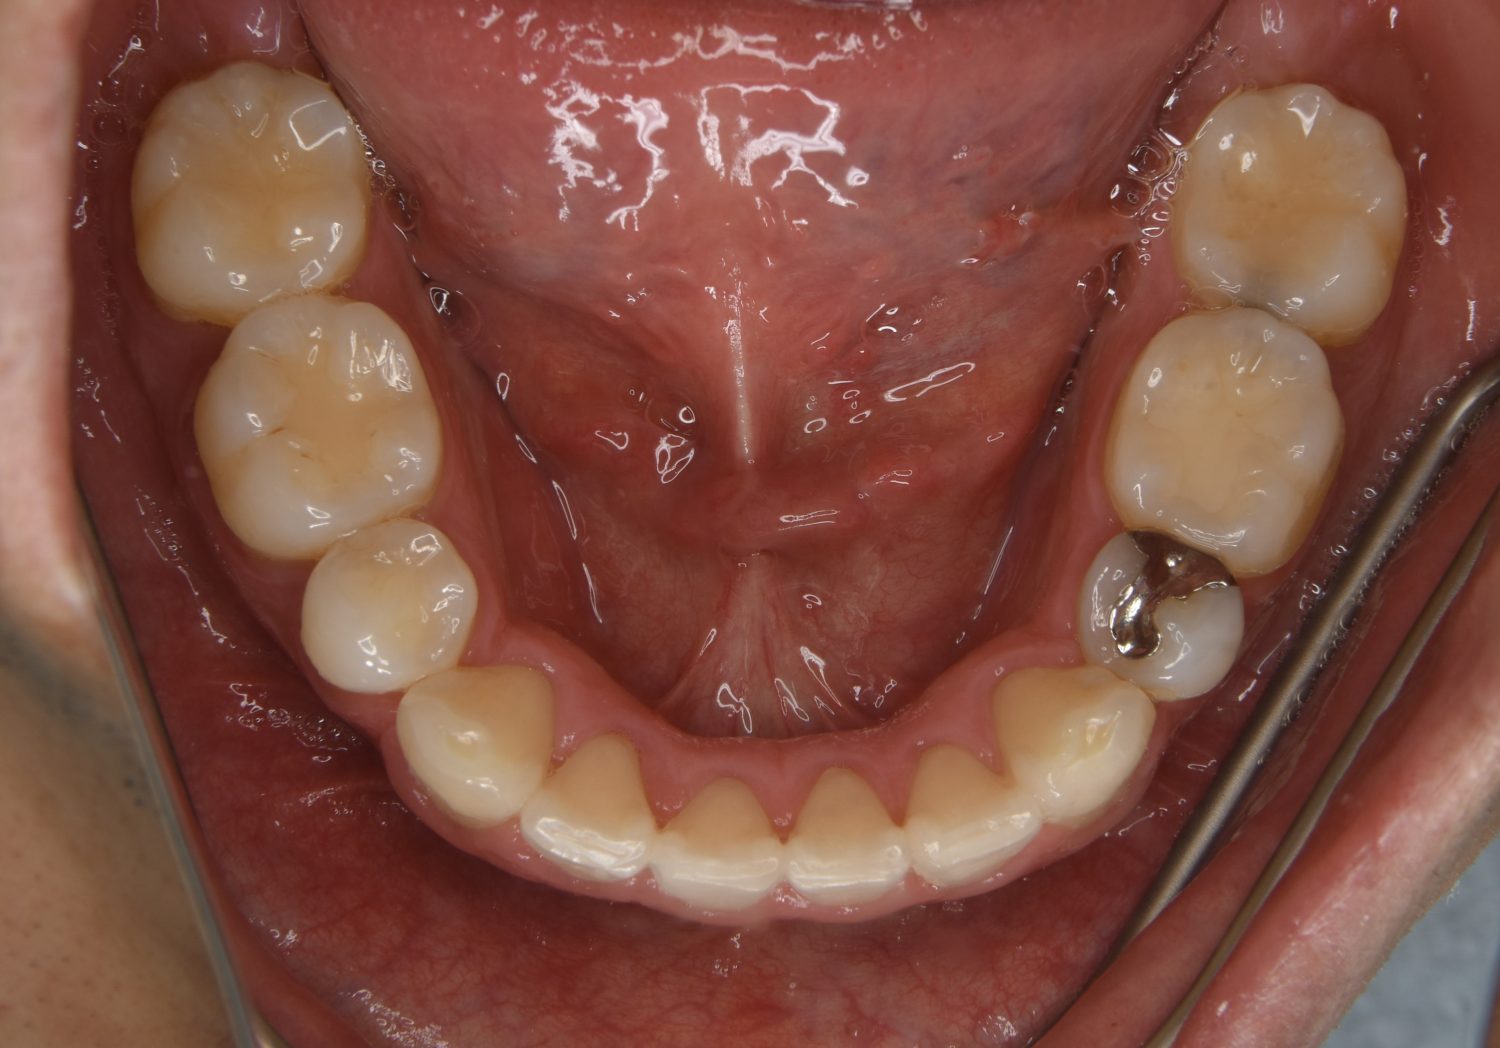

叢生の症例紹介②

Before

After

主訴

歯の凸凹を治したい。

治療内容

アライナー(インビザライン)にて非抜歯で治療を行いました。

治療費

1,150,000 円(税込)

治療期間

26ヶ月

通院回数

14回

想定されたリスク

※歯根吸収、歯肉退縮、歯髄壊死、顎関節症状

※アライナー(インビザライン)は日本の薬機法未承認の矯正装置であり、医薬品副作用被害救済制度の対象外となる場合があります。

丸山和宏先生

ピーススマイル矯正歯科

上下前歯部に叢生(凸凹)が認められる状態でした。歯列の遠心移動を行うことで機能面および審美面が改善されました。